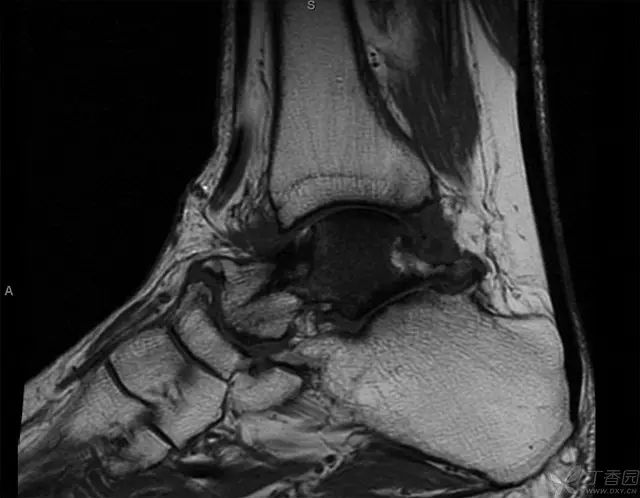

术后 2 周 MRI,没有急性炎症反应

6 个月,有轻度信号改变,表明存在一定程度的生理活动,无骨坏死征象

术后 2 年 MRI,弥漫性信号改变,符合早期骨坏死,但无塌陷

5 年 MRI,弥漫性信号局限在距骨体中心部位,头颈部逐渐出现血运重建,无塌陷